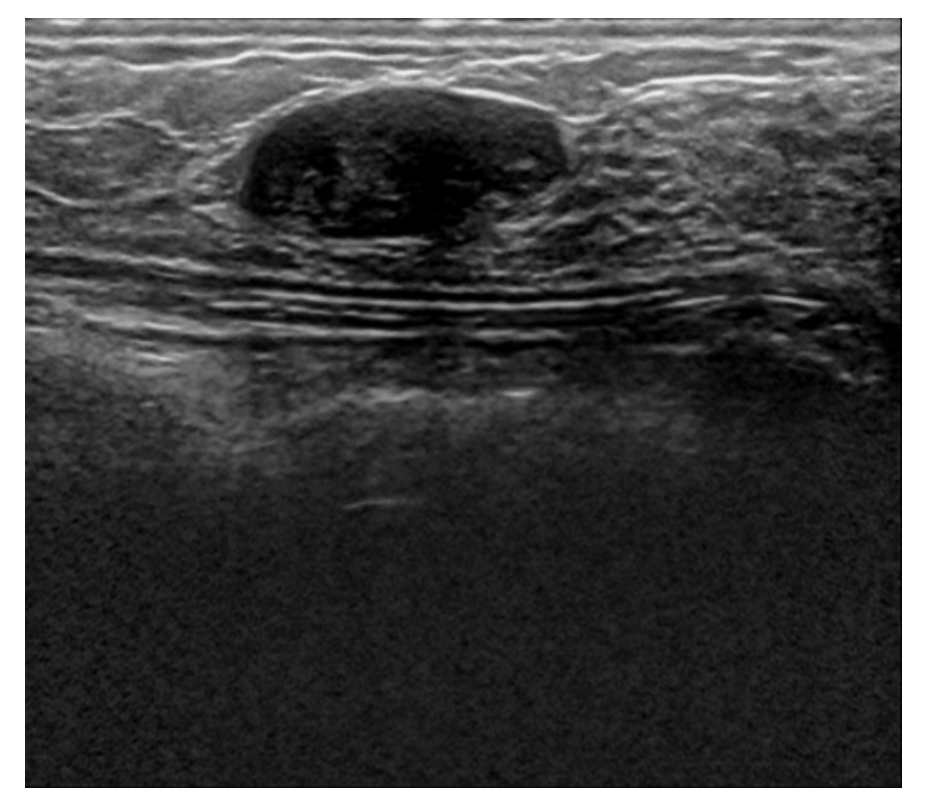

The best PSNR results we have reached so far, as mentioned earlier is (PSNR = 30.44), while at the Median filter, it was (PSNR = 25.362), Gaussian filter (PSNR = 27.541), Average filter (PSNR = 24.934), and Bilateral Filter (PSNR = 23.675), as shown in details at table II, and we can conclude from these results that the CNN Autoencoder is better that the other filtering techniques by 20.02%, 10.52%, 22.08%, and 28.57%, respectively. These results came at an epoch size of 30, batch size of 16, and 256 filters in each of the CNN Layers using the combined dataset which consists of 1568 breast ultrasound images. Below is the training vs validation loss graph , as well as the output image compared to old filtering techniques.

While the best MSE results we have reached so far, is (MSE = 0.0009), while at the Median filter, it was (MSE = 0.0022), Gaussian filter (MSE = 0.0017), Average filter (MSE = 0.0028), and Bilateral Filter (MSE = 0.0034) and we can conclude from these results that the CNN Autoencoder is better than the other filtering techniques. These results came at an epoch size of 50, batch size of 16, and 256 filters in each of the CNN Layers using the combined dataset which consists of 1280 breast ultrasound images, also the same MSE came at an epoch size of 30, batch size 16, and 256 filters in each of the CNN Layers, and a dataset of size 1568 ultrasound images.

The best SSIM results we have reached so far is (SSIM = 93.5%) while at Median filter it was (SSIM = 78.5%), Gaussian filter (SSIM = 87.1%), Average filter (SSIM = 76.9%), and Bilateral Filter (SSIM = 70.7%) and we can conclude from these results that the CNN Autoencoder is better than the other filtering techniques. These results came at an epoch size of 30, batch size of 16, and 256 filters in each of the CNN Layers using the combined dataset which consists of 1568 breast ultrasound images.